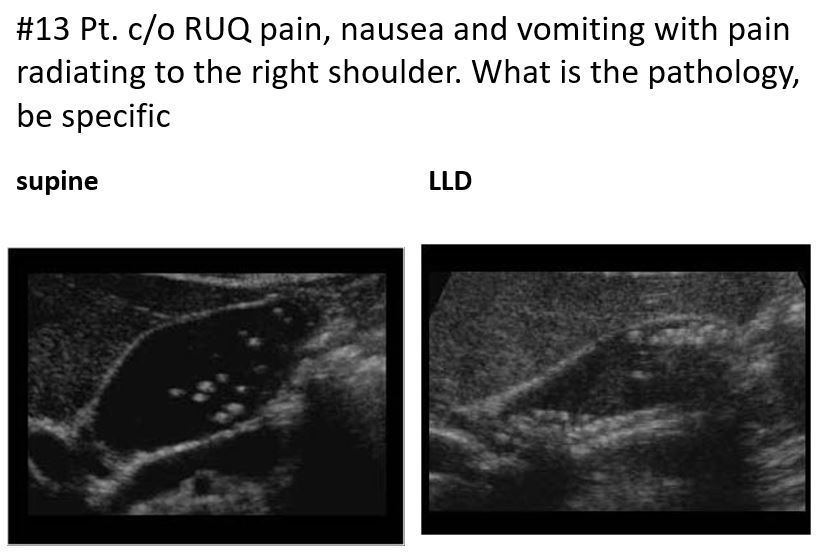

Single, large gallstone or multiple tiny stones

Often asymptomatic

Other factors include pregnancy, diabetes, oral contraceptives, hemolytic diseases, diet-induced weight loss, and total parenteral nutrition (TPN)

After a fatty meal, the gallbladder contracts to release bile; if the outflow tract is blocked by gallstones, then pain results. RUQ Pain, nausea, and vomiting.

The pain can last up to 6 hours

Patients often fall under the category of the “five Fs”: fat, female, forty, fertile, and fair

LAB WORK:AST/ALT MAY BE NORMAL

Elevated bilirubin

Acute Elevated amylase

Elevated ALP

Abnormal LFTs

Cholelithiasis

different patterns of cholelithiasis

Cholelithiasis w Floating Stones

Cholelithiasis showing multiple small floating and

nonfloating gallstones